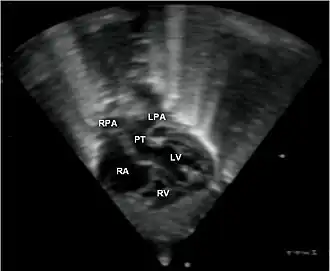

- le signe d'appel habituel est la perte du croisement des gros vaisseaux. Normalement, l'aorte et le tronc pulmonaire se croisent peu après leur sortie du cœur. Il est donc impossible de dérouler les deux vaisseaux sur un même plan de coupe. Quand l'aorte est vue longitudinalement, le tronc pulmonaire n'apparaît qu'en section transversale ("aorte en long, tronc pulmonaire en rond") et vice-versa. Dans la D-TGV simple, la plus fréquente, les vaisseaux ont un trajet parallèle et peuvent donc être visualisés longitudinalement simultanément.

- la confirmation est obtenue par l'analyse des gros vaisseaux et de leurs connexions aux ventricules. L'aorte est caractérisée par le fait qu'elle décrit une crosse, donne naissance aux vaisseaux à destinée céphalique et est le vaisseau qui monte le plus haut dans le thorax. Le tronc pulmonaire est caractérisé par sa bifurcation précoce en deux branches, les artères pulmonaires droite et gauche. Sur un cœur par ailleurs normal, le ventricule droit est situé en avant et à droite du ventricule gauche, le tronc pulmonaire est donc le vaisseau le plus antérieur. La TGV se caractérise par la position antérieure du vaisseau qui décrit la crosse et donne les vaisseaux céphaliques : l'aorte.

- Les coupes échographiques les plus utiles à cette fin sont :

- La coupe parasternale gauche grand axe : elle montre que le vaisseau issu du ventricule gauche (le plus postérieur) se dirige anormalement vers l'arrière et se bifurque précocement. C'est donc le tronc pulmonaire et non l'aorte comme normalement.

- Les coupes sous costales qui montrent bien le trajet parallèle des gros vaisseaux et leur inversion. Cet examen permettra d'éliminer en particulier un retour veineux pulmonaire anormal total bloqué qui aurait pu rendre compte de l’hypervascularisation pulmonaire sur la radiographie des poumons.